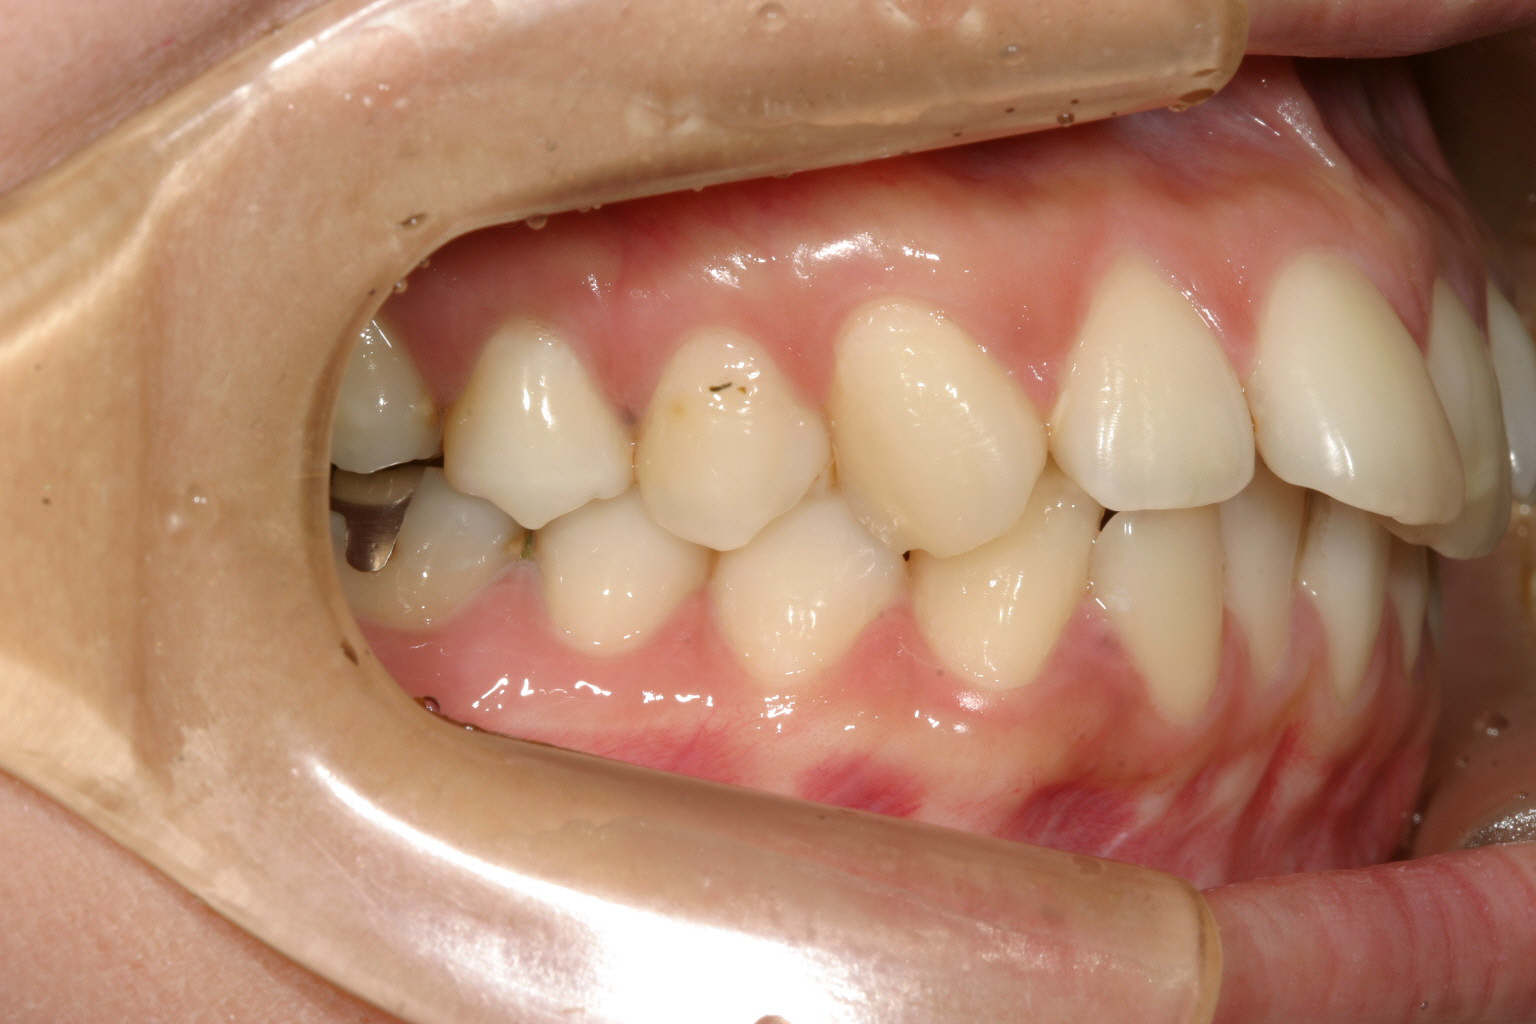

側面観も大変綺麗になりました。